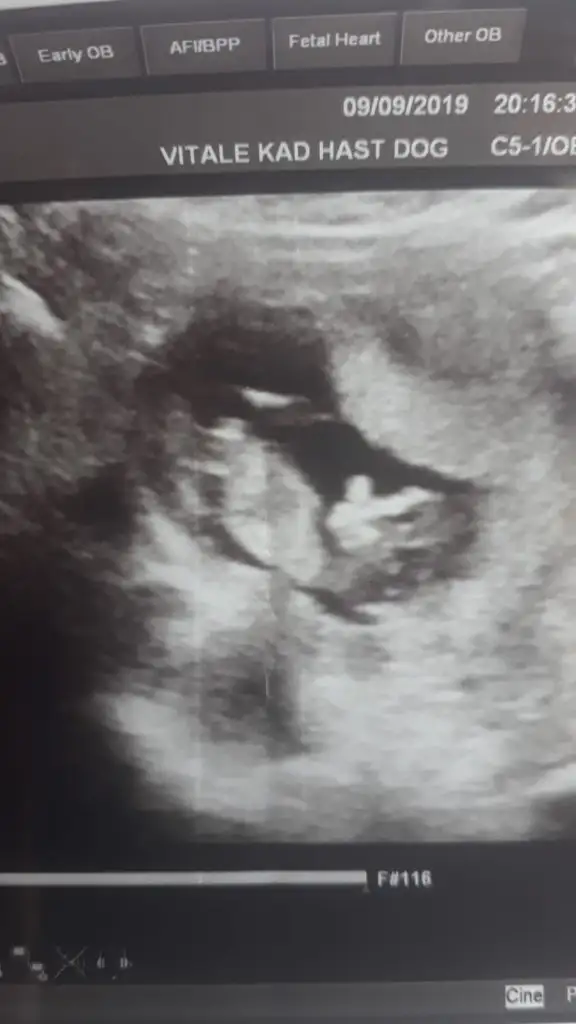

Erkek mi?Merhaba bize de tahminde bulunabilir misiniz? Karından usg

Kaç haftalık tam net degil başka varsa tahmin ederimMerhaba benim için de cinsiyet tahmini yapabilir misiniz?